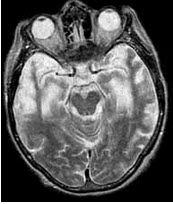

66、单项选择题

一痴呆患者有明显的人格改变和行为障碍,定向力和记忆力尚好,头颅MRIT表现如图。该患者最可能的诊断为()

A.Alzheimer病

B.抑郁症

C.Pick病

D.血管性痴呆

E.路易体痴呆

111、填空题

根据如图提示,Pick病患者CT、MRI主要表现为________。